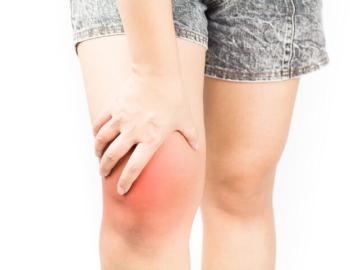

Uobičajeno znan kao artritis trošenja zgloba ( slika 1 ), OA je stanje kod kojeg je došlo do trošenja hrskavice između koštanih struktura u zglobu. Kada se taj proces razvije dolazi do struganja površine kostiju jedna od drugu uz smanjenu sposobnost apsorbiranja udaraca. To struganje uzrokuje pojavu boli, otečenost, ukočenost, ograničenu pokretljivost te ponekad i razvoj koštanih izdanaka OA koljena je najčešći oblik OA ( slika 2 ). Iako se može javiti kod mlađih ljudi, ipak rizik za razvoj istoga se povećava nakon 45.god života, s time da su žene sklonije razvoju.

•bol koja se pojačava sa pokretom i aktivnošću a nešto se smiruje u mirovanju ( slika 4 )